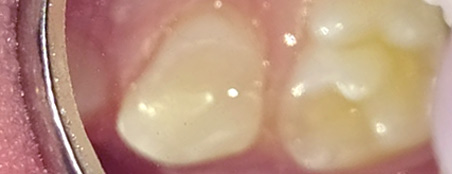

Эстетические реставрации. Дошколятам нравятся цветные пломбы, а детям постарше врач поставит пломбу, точь-в-точь совпадающую по цвету, форме и рельефу с натуральным зубом.

Наши работы